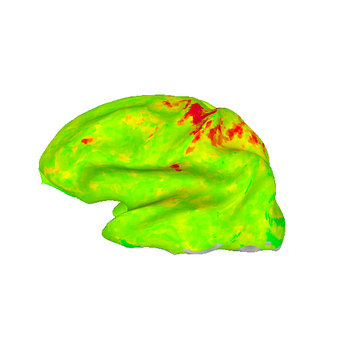

Measuring the effectiveness of motion and distortion correction

A quantitative way to judge the effectiveness of motion and distortion correction is to analyse fMRI activation maps created from EPI data; if motion and distortion correction is successful, the significance of the observed activation should, in general, be higher. For the sample dataset above (case CW) here is the F-statistic of the most significant voxel:

No motion or distortion correction: peak F = 8.91

No motion correction, distortion correction applied independently to every image:peak F = 8.88

Motion but not distortion correction: peak F = 9.11

Motion and distortion correction (as above, motion corrected to EPI image closest in time to anatomy): peak F = 9.76

Motion and distortion correction (motion corrected to mean EPI image): peak F = 9.86

These images show lateral views of surface models. The colors represent the F-statistic at each surface node for each of the motion and distortion correction methods. While there are differences between the images, they are subtle.